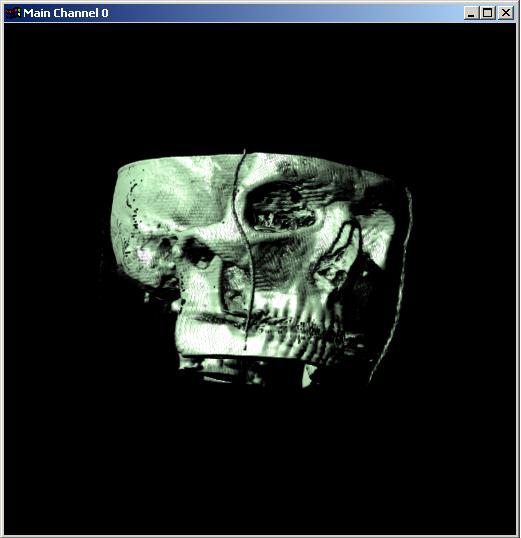

Visible human male CT data

Shaded head

with bone

Data Resolution : 512x512x256

The following 12

images was generated by PC which has NVIDIA's GeForce3 GPU graphics card. The

hardware accelerated rendering techniques are used to make the following images.

To use the GeForce3 hardware, we have to use the OpenGL extensions like

GL_NV_texture_shader2, GL_NV_register_combiners, GL_EXT_texture3D,

GL_EXT_paletted_texture, GL_ARB_multitexture and so on. Since the GeForce3 card

allows the 3D texture shading, the image quality is better than the pixel of

frame buffer based shading in showing two materials at the same time.